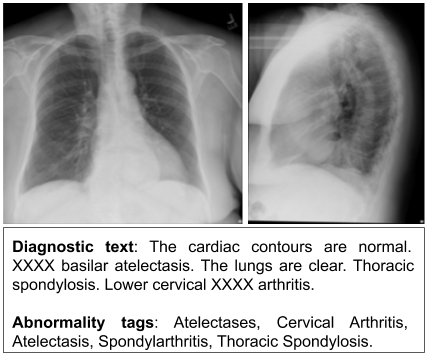

Figure 1. A PA/lateral chest radiography exam along with the corresponding human-authored diagnostic text from IU X-Ray, and the abnormality tags. The ‘XXXX’ is due to the de-identification process.

Medical imaging is the method of forming visual representations of the anatomy or a function of the human body using a variety of imaging modalities (e.g., CR, CT, MRI) (Suetens, 2009; Aerts et al., 2014). In this paper, we particularly focus on chest radiography exams, which contain medical images produced by X-Rays. It is estimated that over three billion radiography exams are performed annually worldwide (Krupinski, 2010), making the daily need for processing and interpretation of the produced radiographs paramount. An example of a radiography exam is provided in Fig. 1, that consists of two chest radiographs together with the diagnostic text, describing the medical observations on the radiographs, and a list of abnormality tags indicating most critical observations in the exam. In the diagnostic text, we observe that two findings are normal (i.e., cardiac contours and lungs), while three are abnormal, i.e., thoracic spondylosis, lower cervical arthritis, and basilar atelectasis. These abnormal findings are also consistent with the abnormality tags.